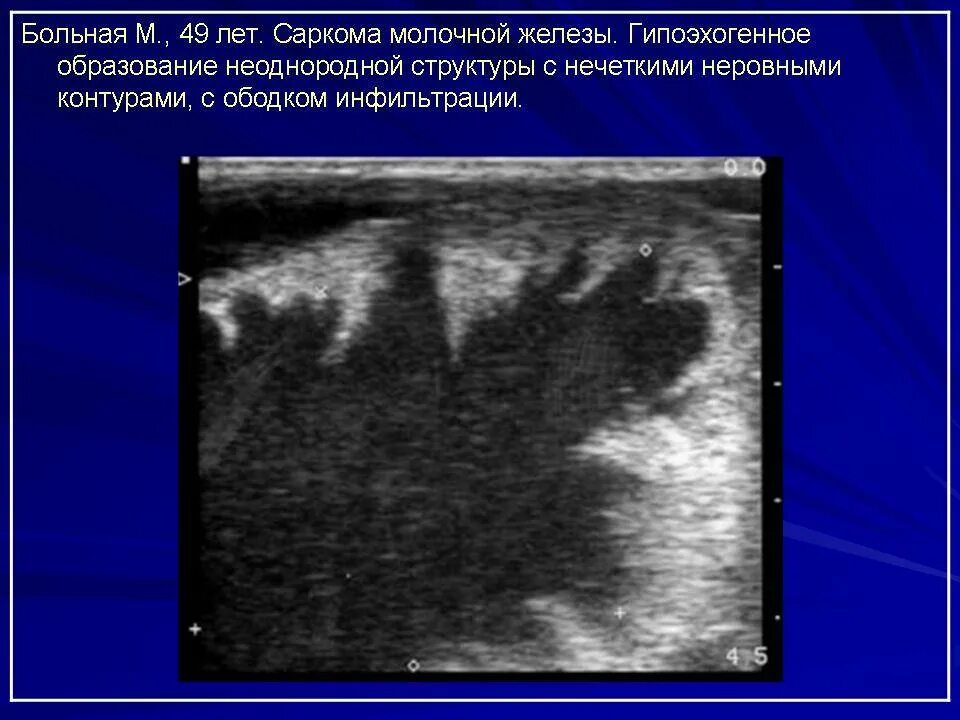

Как выглядит фиброаденома молочной железы